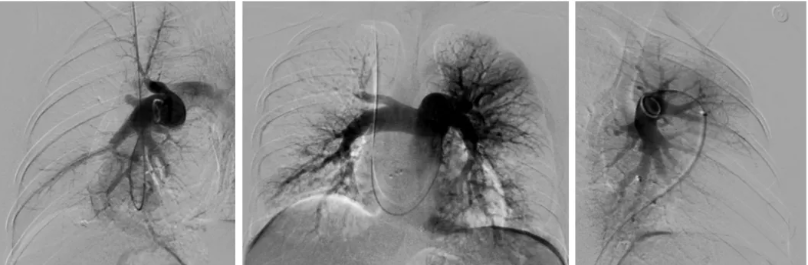

图8 2024.11.12 肺动脉造影(正位,左右45°斜位)

右心导管检查结果示(图7):mPAP 47/16(26)mmHg,CI 3.2L/min/m2,PVR 4.7WU,SvO2:51.3%。肺动脉造影可见(图8):肺动脉主干增粗,双侧肺动脉及其分支广泛狭窄、闭塞病变,远端血流差,以RA1、RA2、RA3、RA4、RA5、RA10、LA4、LA5、LA8为著。据此,CTEPH诊断明确。